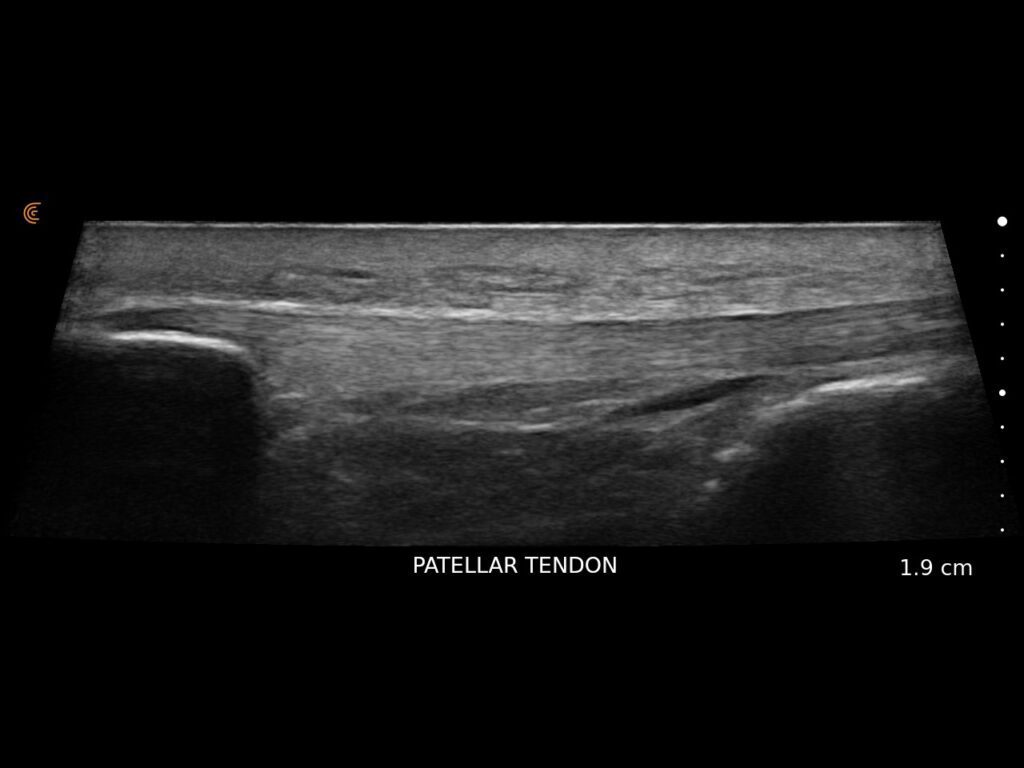

Visualize targets in real time to deliver PRP or cortisone—even in complex joints. Instantly diagnose sprains, tears, and effusions, and make confident decisions about surgical intervention

Get Athletes Back in Action – Faster.

Specialized presets and high resolution provide fast, accurate imaging for athletes’ needs.